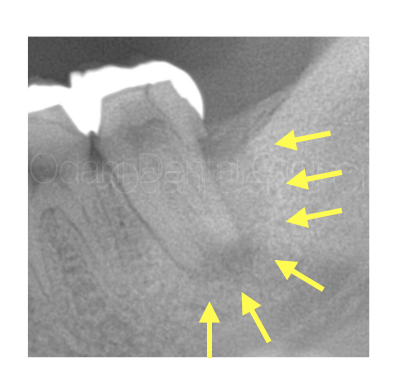

診察および画像検査の結果、歯の周囲を大きく取り囲むような黒い影(黄色の矢印)が確認できました。

詰め物を外すと中で大きな虫歯が生じており(赤矢印)、そこから神経が死んでしまい、歯の周囲にまで細菌感染している状態だと判断できました。骨の支えが大きく失われており、歯は大きく揺れておりました。

CT画像では、歯の根の周囲の骨が大きく吸収していることが確認でき、それに伴い歯ぐきの腫れや、歯周ポケットが10mm以上と深い状態になっていました。